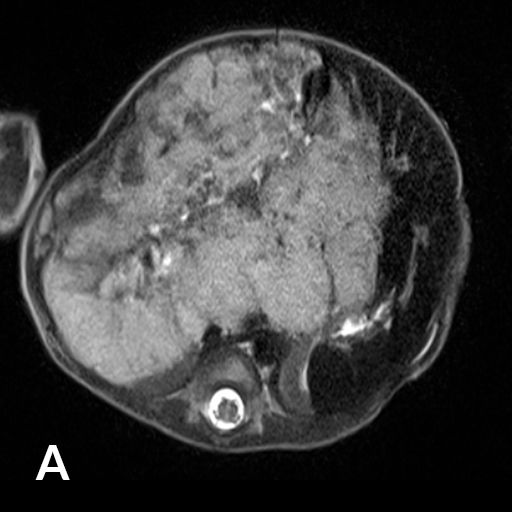

8 jähriger Junge nach Transplantation der linksseitigen Lebersegmente

In der Bildgebung (MRCP-Bild, A) zeigt sich eine Erweiterung der Gallenwege in der Leber, bedingt durch eine Engstelle an der Verbindung der Gallenwege (Gallenwegsanastomose). Entlastung der gestauten Gallenwege mittels PTCD. Punktion eines in der Leber gelegenen Gallenweges mit Hilfe von Ultraschall. Gabe von Kontrastmittel über die Punktionsnadel (B). Darstellung des gestauten Gangsystems und der Engstelle (Pfeil). Anschließende Anlage einer Ableitung (Drainage) zur Entlastung des Gallenwegssystems (C).

Abb 1

A